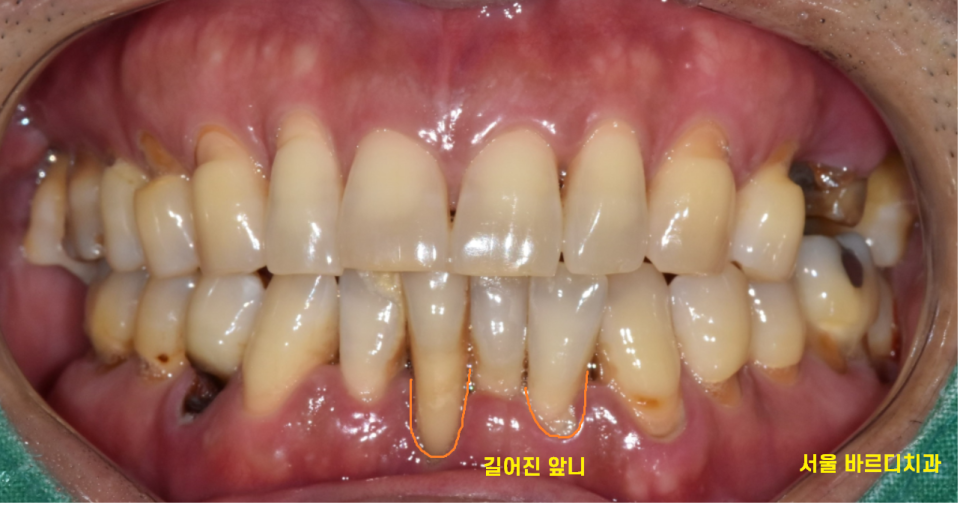

환자분께서는 거울을 보시면서

불편하기도 불편한데

앞니가 길어져서 보기 싫다고 하시더라고요~

문제는 치아 잇몸뼈가 너무 녹아서...

뼈가 없었습니다.